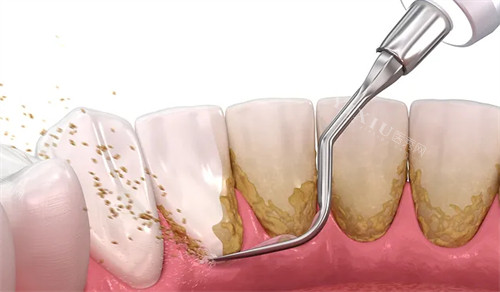

洗牙套餐:68元起